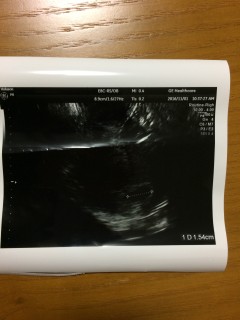

5日前に11.5mmの胎嚢を確認。 一週間後にまた来てくださいと言われましたが、キリキリとした下腹部痛と少量の出血があったため予定より早く病院へ。この日に14.8mmの胎のうと、卵黄嚢、胎芽を確認できました(*・∀・) 先生いわく「血は止まってるから大丈夫!赤ちゃんの心臓も動きはじめてるよ」とのことでしたが・・・私には小さすぎてわからず(笑) 次回はしっかり確認できるかな? 食べつわりでしんどいけど頑張ります(´・ω・`)